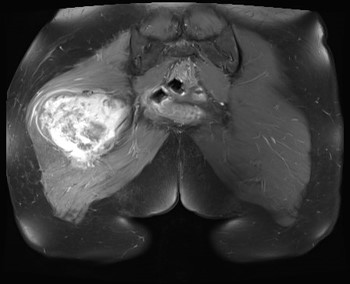

MRI

Sarcoma buttock